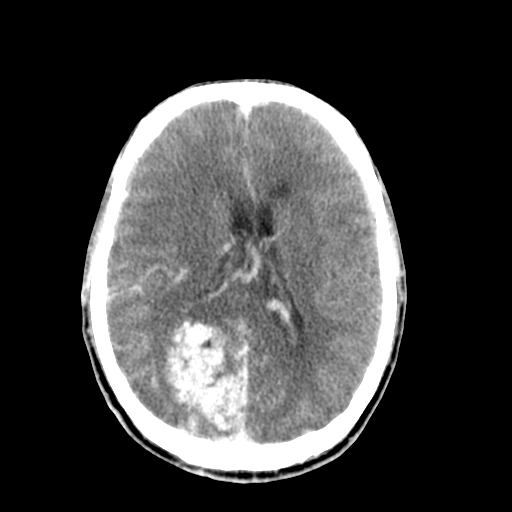

标题: CT17002:M48Y,血管畸形,血管瘤,请鉴赏! [打印本页]

男48y,头痛多年,加重一天!

典型的血管畸形---avm  -----右侧枕顶叶及侧脑室三角区等高混杂密度影夹杂少许低密影显示,无明显水肿,增强可见明显的供血动脉与引流静脉显示